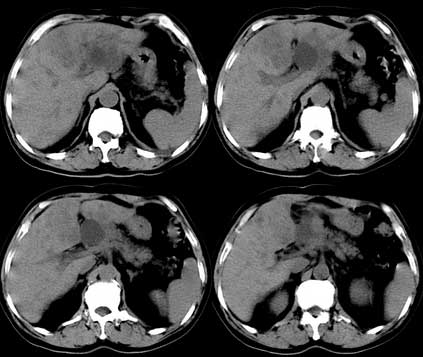

患者 男性 65岁,2005年8月行胆管癌切除术(切除胰头 胆囊及十二指肠),今行ct复查,请会诊,有没有复发?(近期患者发烧,重度黄疸)

是单纯复发还是复发伴肝内转移?我个人认为应当再考虑一下,并倾向于后者。肝总管下端内、后侧见不规则软组织块影,部分侵入肝总管内。其边缘凸凹不平且模糊不清,渐进性不均匀强化。肝总管于此处管径突然变小,其上肝总管显著扩张,内见较均匀液性密度,管壁也很光整。肝内多发低密度病灶用复发引起的肝内胆管扩张显然不能解释的通,病灶分布与胆内胆管的走行不一致。而且随着时间的延续病变更加清晰,没有强化,部分还可见牛眼征。

肯定是:胆管复发并肝内广泛转移,还有肝及胆总管周围网膜炎性改变。腹腔干后第三层面腹膜后血管间结节状影,淋巴结肿大可能,这上面没法看清!

考虑复发并转移,肝门区胆管扩张,左肾多发囊肿可能.腹腔淋巴结转移.

复发,转移,左肾多发囊肿腹腔淋巴tb